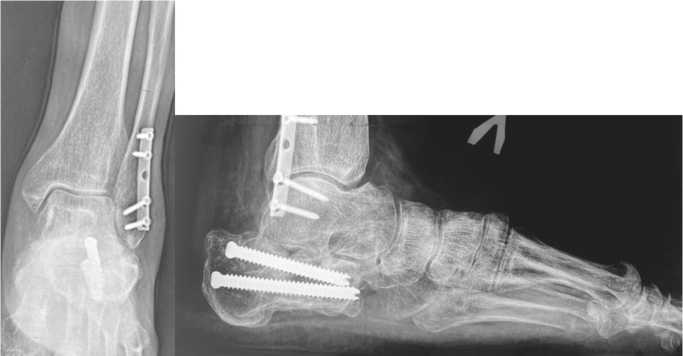

После изготовления индивидуального резекционного блока пациенту выполнено оперативное вмешательство с применением разработанного нами метода, в ходе которого достигнута планируемая коррекция деформации (рис. 8). Учитывая выраженное натяжение ахиллова сухожилия после репозиции костных фрагментов, пациенту осуществлена чрескожная ахиллотомия по Вульпиусу, в результате чего удалось достичь практически полного восстановления объема движений в левом голеностопном суставе.

Рис. 8. Интраоперационный ЭОП-контроль в передне-задней и боковой проекциях

Коррекция деформации пяточной кости выполнена в соответствии с предоперационным планированием. Положение костных фрагментов и установленной металлоконструкции оценено как удовлетворительное.

Послеоперационный период у пациента протекал без осложнений, рана зажила первичным натяжением, швы сняты на 21-й день после операции. С учетом успешного заживления раны и устранения послеоперационного отека гипсовая повязка заменена на циркулярную полимерную с продолжением иммобилизации сроком на два месяца. По истечении этого периода пациенту проведен контрольный осмотр, включающий оценку рентгеновских снимков и данных МСКТ оперированной левой пяточной кости. Проведенные диагностические мероприятия подтвердили успешное костное сращение артифи-циального перелома левой пяточной кости, формирование подтаранного костного блока и стабильное положение металлоконструкций. После этого пациенту была разрешена дозированная нагрузка на оперированную конечность и назначено восстановительное-реабилитационное лечение, включавшее в себя физиотерапию, массаж и лечебную физкультуру в условиях реабилитационного центра.

В течение месяца осевая нагрузка на конечность была полностью восстановлена, что позволило пациенту вернуться к трудовой деятельности. Динамическое наблюдение за пациентом продолжали, окончательный результат лечения оценен через 12 месяцев после операции. На контрольном осмотре отмечено сохранение достигнутой коррекции заднего отдела левой стопы, отсутствие латерального пяточно-малоберцового импиджмента, восстановление угла отклонения таранной кости, угла наклона пяточной кости, угла Мири, лодыжечного роста и ширины пяточной кости (рис. 9, а). Результаты МСКТ демонстрировали консолидированный артифициальный перелом левой пяточной кости с формированием подтаранного костного блока в условиях фиксации винтами, а также консолидированный перелом малоберцовой кости в условиях фиксации блокируемой пластиной (рис. 9, б).

Рис. 9. Результаты рентгенографии и МСКТ визуализации левой стопы пациента через 12 мес. после оперативного вмешательства: рентгенограммы в прямой и боковой проекциях, выполненная в условиях нагрузки весом тела (а), МСКТ-реконструкция в коронарной, сагиттальной и аксиальной плоскостях (б)